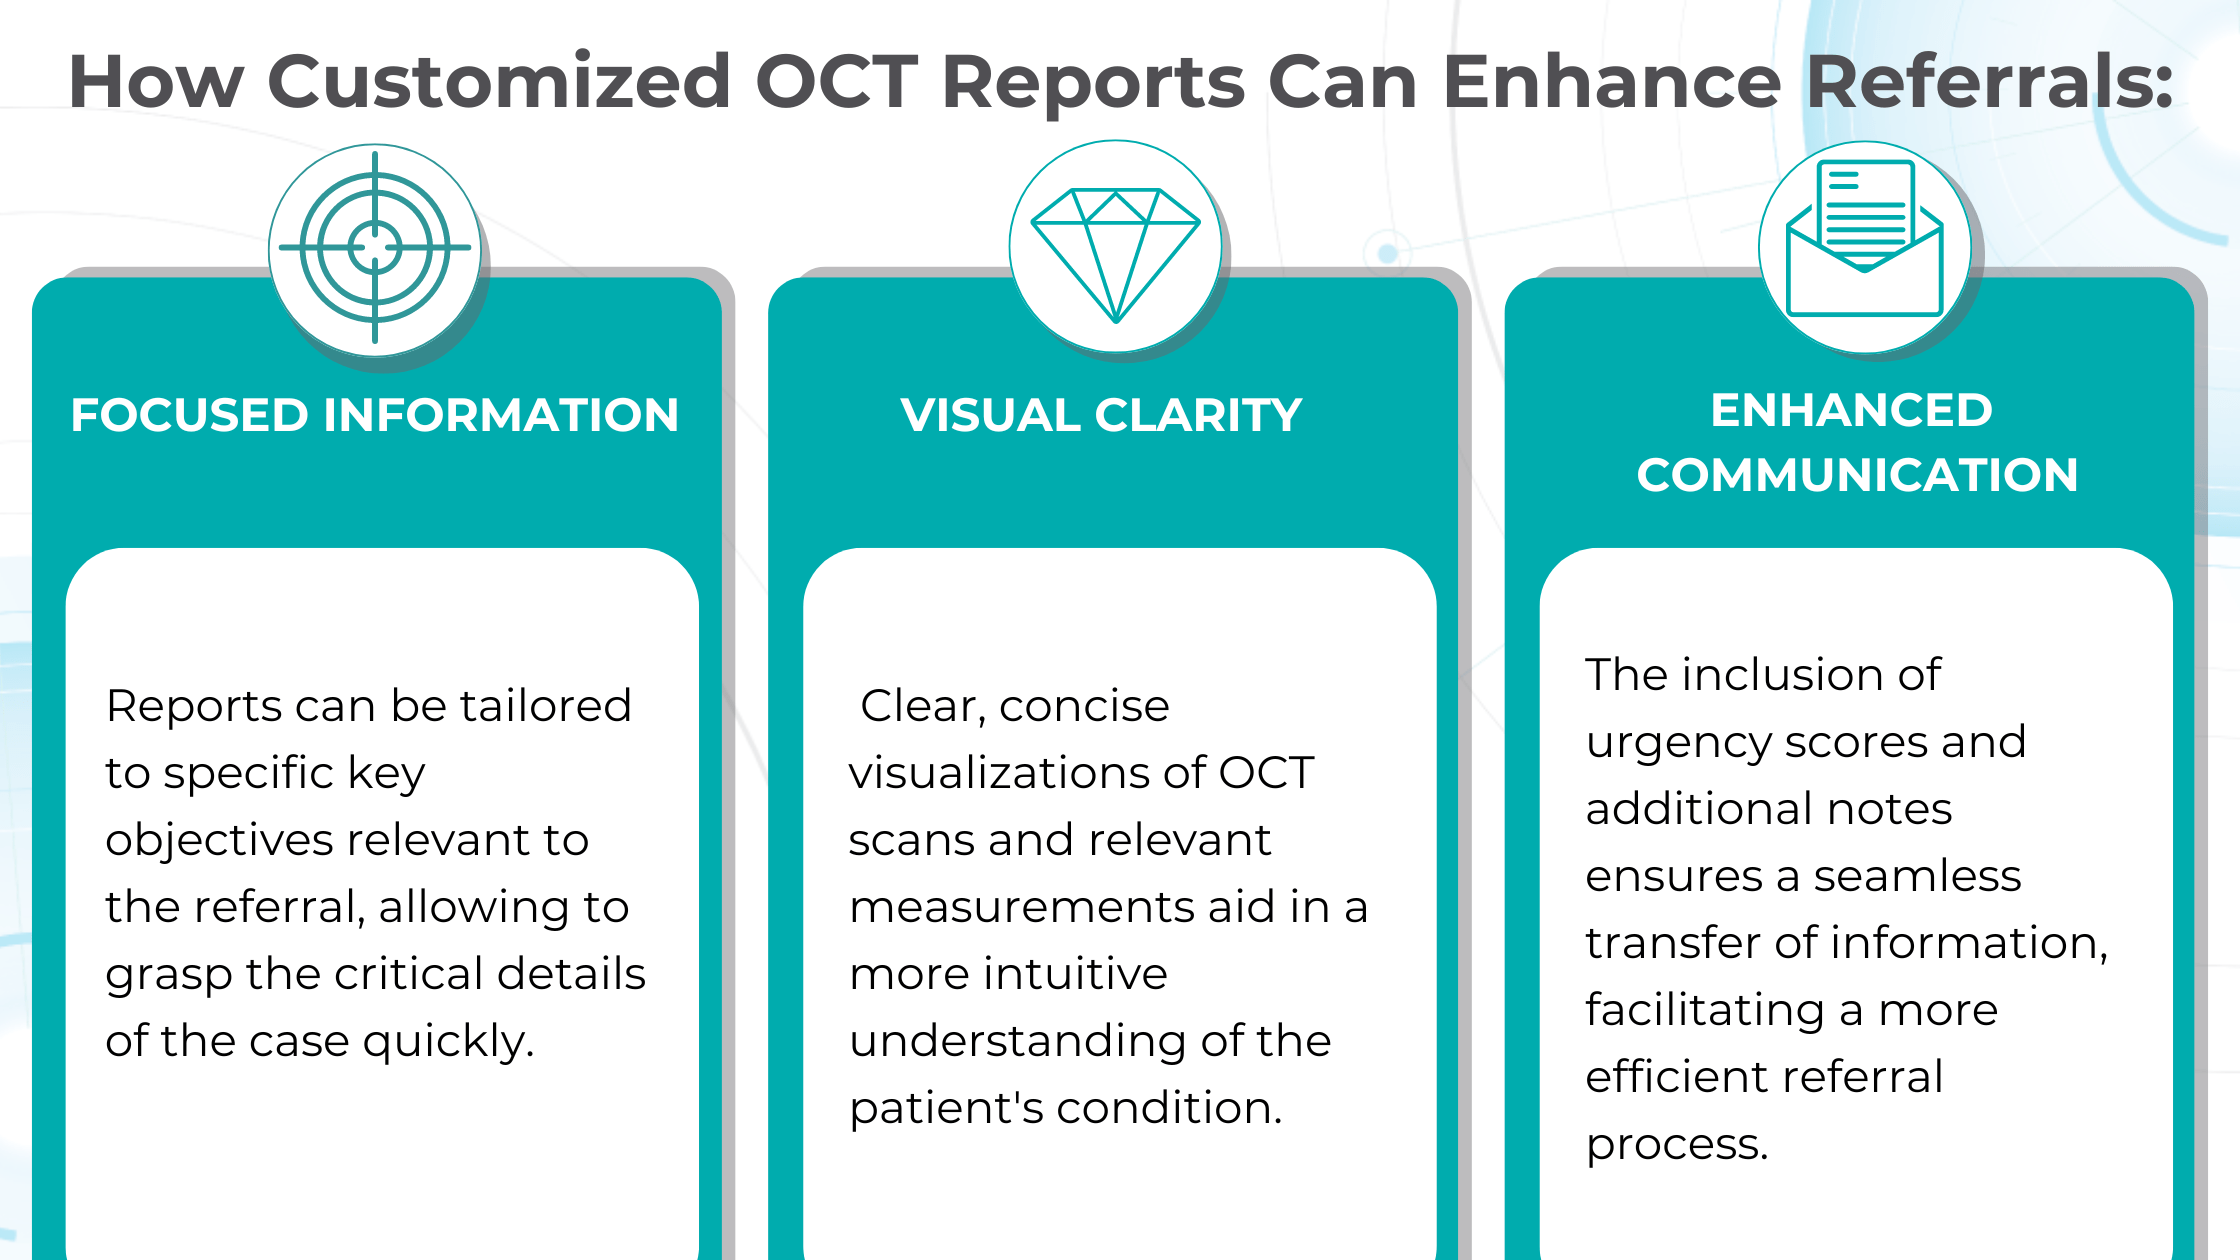

Crafting effective referral

In the UK, optometrists are crucial in initiating referrals to hospital eye services (HES), with 72% originating from primary care optometric examinations. While optometrists generally demonstrate proficiency in identifying conditions like cataracts and glaucoma, discrepancies in referral thresholds and unfamiliarity with less common pathologies can lead to unnecessary or delayed referrals.

At the same time, an evaluation of incoming letters from optometrists in a glaucoma service found that 43% of the letters were considered “failures” because they did not convey the necessity and urgency of the referral.

So, having an elaborate record of the entire clinical examination in addition to a referral letter is crucial.

Customized OCT reports solve this challenge by streamlining the referral process and improving communication between optometrists and ophthalmologists. These reports can significantly reduce delays and ensure patients receive timely care by providing comprehensive and relevant information upfront.

Customisable OCT reports aid in the early detection and monitoring of diseases like wet AMD and glaucoma, empowering clinicians with accurate diagnoses and personalized treatment plans. Additionally, they streamline referrals by providing focused information and clear visualizations, reducing delays and improving communication between optometrists and ophthalmologists.